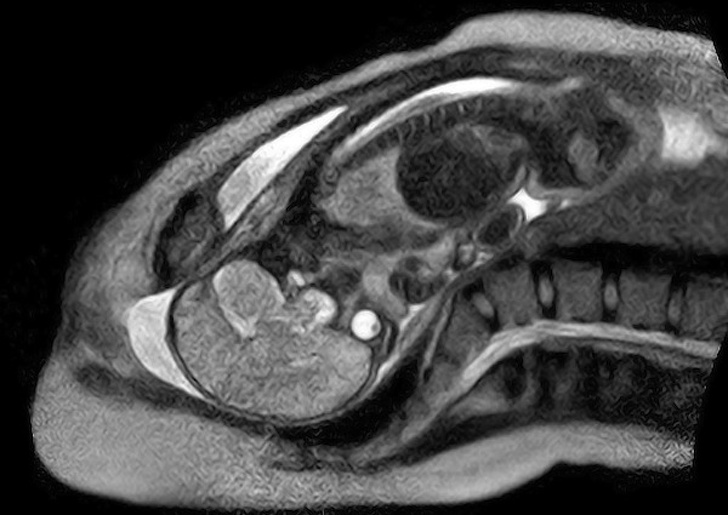

18. Пологи в апараті МРТ